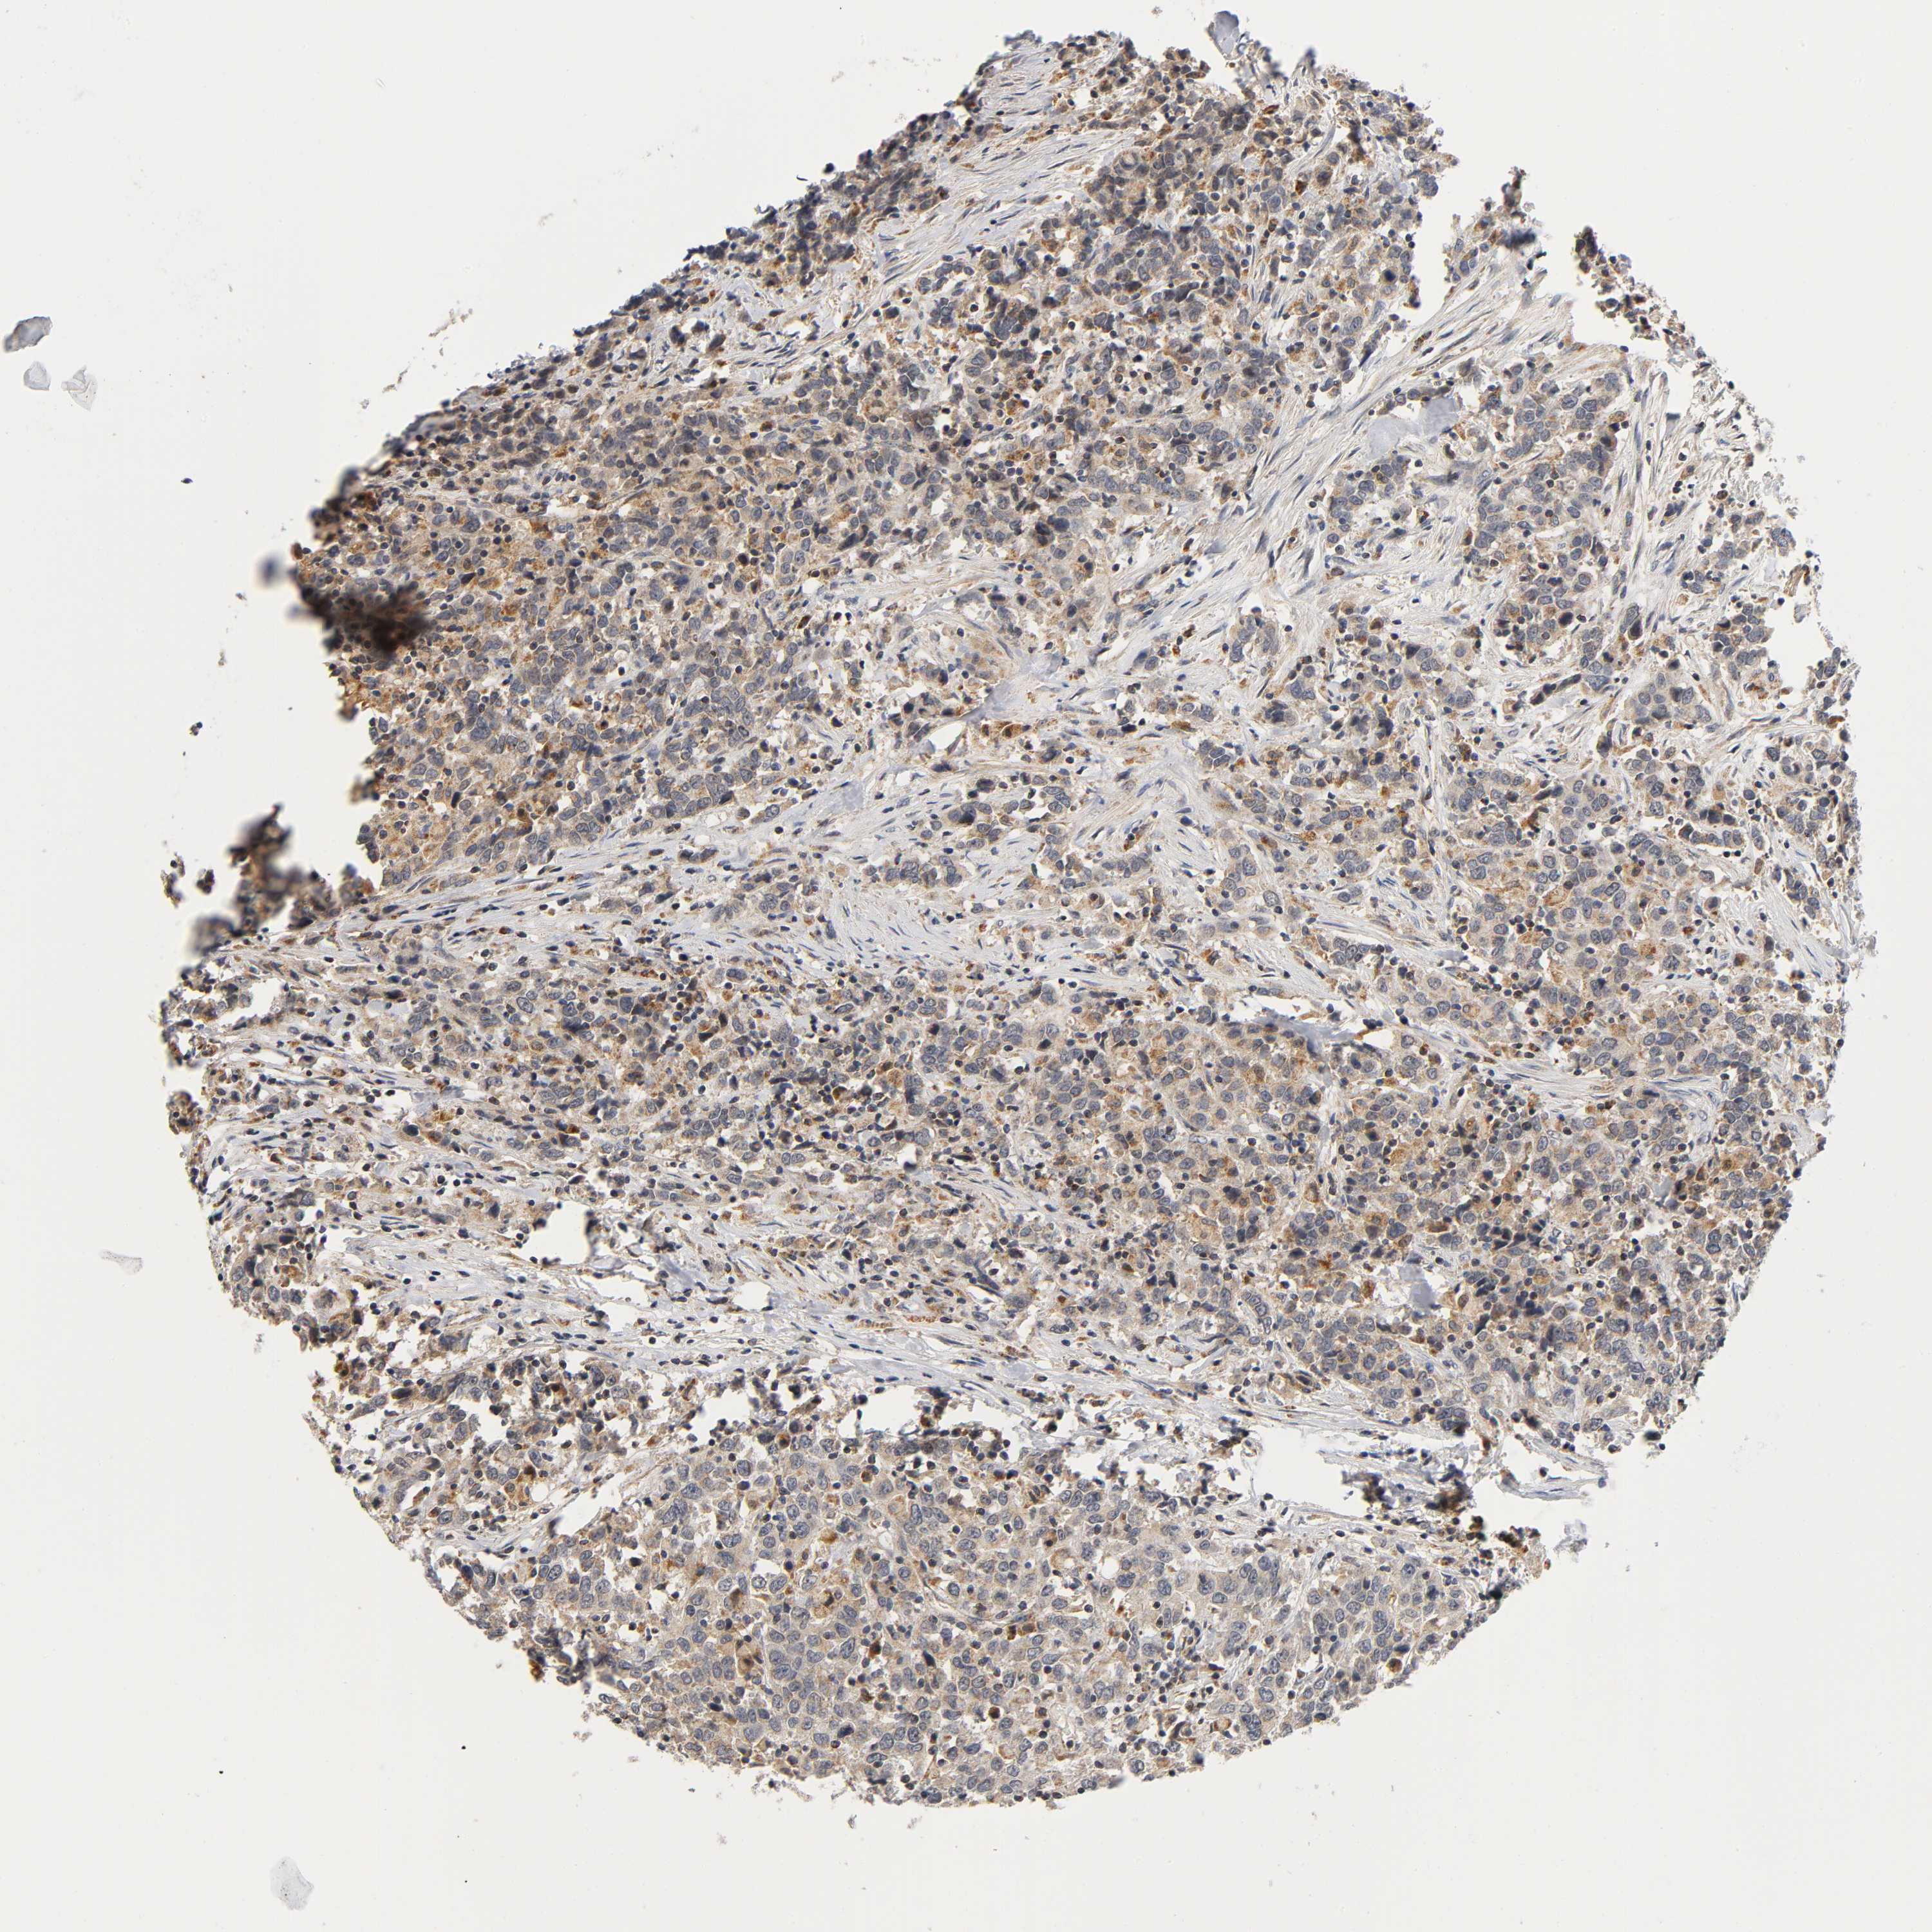

UROTHELIAL CANCER - Protein expressioni

A mouse-over function shows sample information and annotation data. Click on an image to view it in a full screen mode. Samples can be filtered based on level of antibody staining by selecting one or several of the following categories: high, medium, low and not detected. The assay and annotation is described here.

Antibody stainingi

Antibody staining in the annotated cell types in the current human tissue is reported as not detected, low, medium, or high, based on conventional immunohistochemistry profiling in selected tissues. This score is based on the combination of the staining intensity and fraction of stained cells.

Each image is clickable and will lead to virtual microscopy that enables deeper exploration of all samples and also displays staining intensity scores, fraction scores and subcellular localization as well as patient and tissue information for each sample.

Antibody HPA030278

Antibody CAB004511

Urothelial carcinoma, Low grade

Urothelial carcinoma, High grade